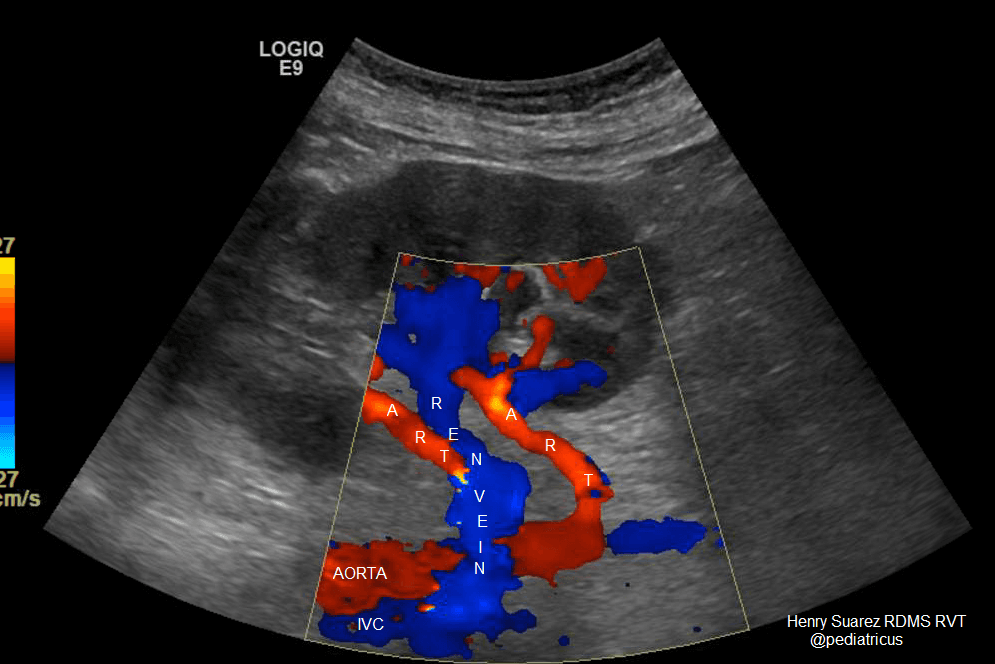

Renal Artery Doppler

Doppler ultrasound for renal artery stenosis detection

Renal Artery Stenosis Detection

Blood Flow Measurement

Hypertension Evaluation

Kidney Function Assessment